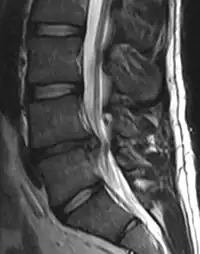

In most episodes, a specific underlying cause is not identified or even looked for, with the pain believed to be due to mechanical problems such as muscle or joint strain.[1][4] If the pain does not go away with conservative treatment or if it is accompanied by "red flags" such as unexplained weight loss, fever, or significant problems with feeling or movement, further testing may be needed to look for a serious underlying problem.[5] In most cases, imaging tools such as X-ray computed tomography are not useful and carry their own risks.[9][10] Despite this, the use of imaging in low back pain has increased.[11] Some low back pain is caused by damaged intervertebral discs, and the straight leg raise test is useful to identify this cause.[5] In those with chronic pain, the pain processing system may malfunction, causing large amounts of pain in response to non-serious events.[12]

Tests

Imaging is indicated when there are red flags, ongoing neurological symptoms that do not resolve, or ongoing or worsening pain.[5] In particular, early use of imaging (either MRI or CT) is recommended for suspected cancer, infection, or cauda equina syndrome.[5] MRI is slightly better than CT for identifying disc disease; the two technologies are equally useful for diagnosing spinal stenosis.[5] Only a few physical diagnostic tests are helpful.[5] The straight leg raise test is almost always positive in those with disc herniation.[5] Lumbar provocative discography may be useful to identify a specific disc causing pain in those with chronic high levels of low back pain.[43] Similarly, therapeutic procedures such as nerve blocks can be used to determine a specific source of pain.[5] Some evidence supports the use of facet joint injections, transforminal epidural injections and sacroilliac injections as diagnostic tests.[5] Most other physical tests, such as evaluating for scoliosis, muscle weakness or wasting, and impaired reflexes, are of little use.[5]

Complaints of low back pain are one of the most common reasons people visit doctors.[9][44] For pain that has lasted only a few weeks, the pain is likely to subside on its own.[45] Thus, if a person's medical history and physical examination do not suggest a specific disease as the cause, medical societies advise against imaging tests such as X-rays, CT scans, and MRIs.[44] Individuals may want such tests but, unless red flags are present,[10][46] they are unnecessary health care.[9][45] Routine imaging increases costs, is associated with higher rates of surgery with no overall benefit,[47][48] and the radiation used may be harmful to one's health.[47] Fewer than 1% of imaging tests identify the cause of the problem.[9] Imaging may also detect harmless abnormalities, encouraging people to request further unnecessary testing or to worry.[9] Even so, MRI scans of the lumbar region increased by more than 300% among United States Medicare beneficiaries from 1994 to 2006.[11]